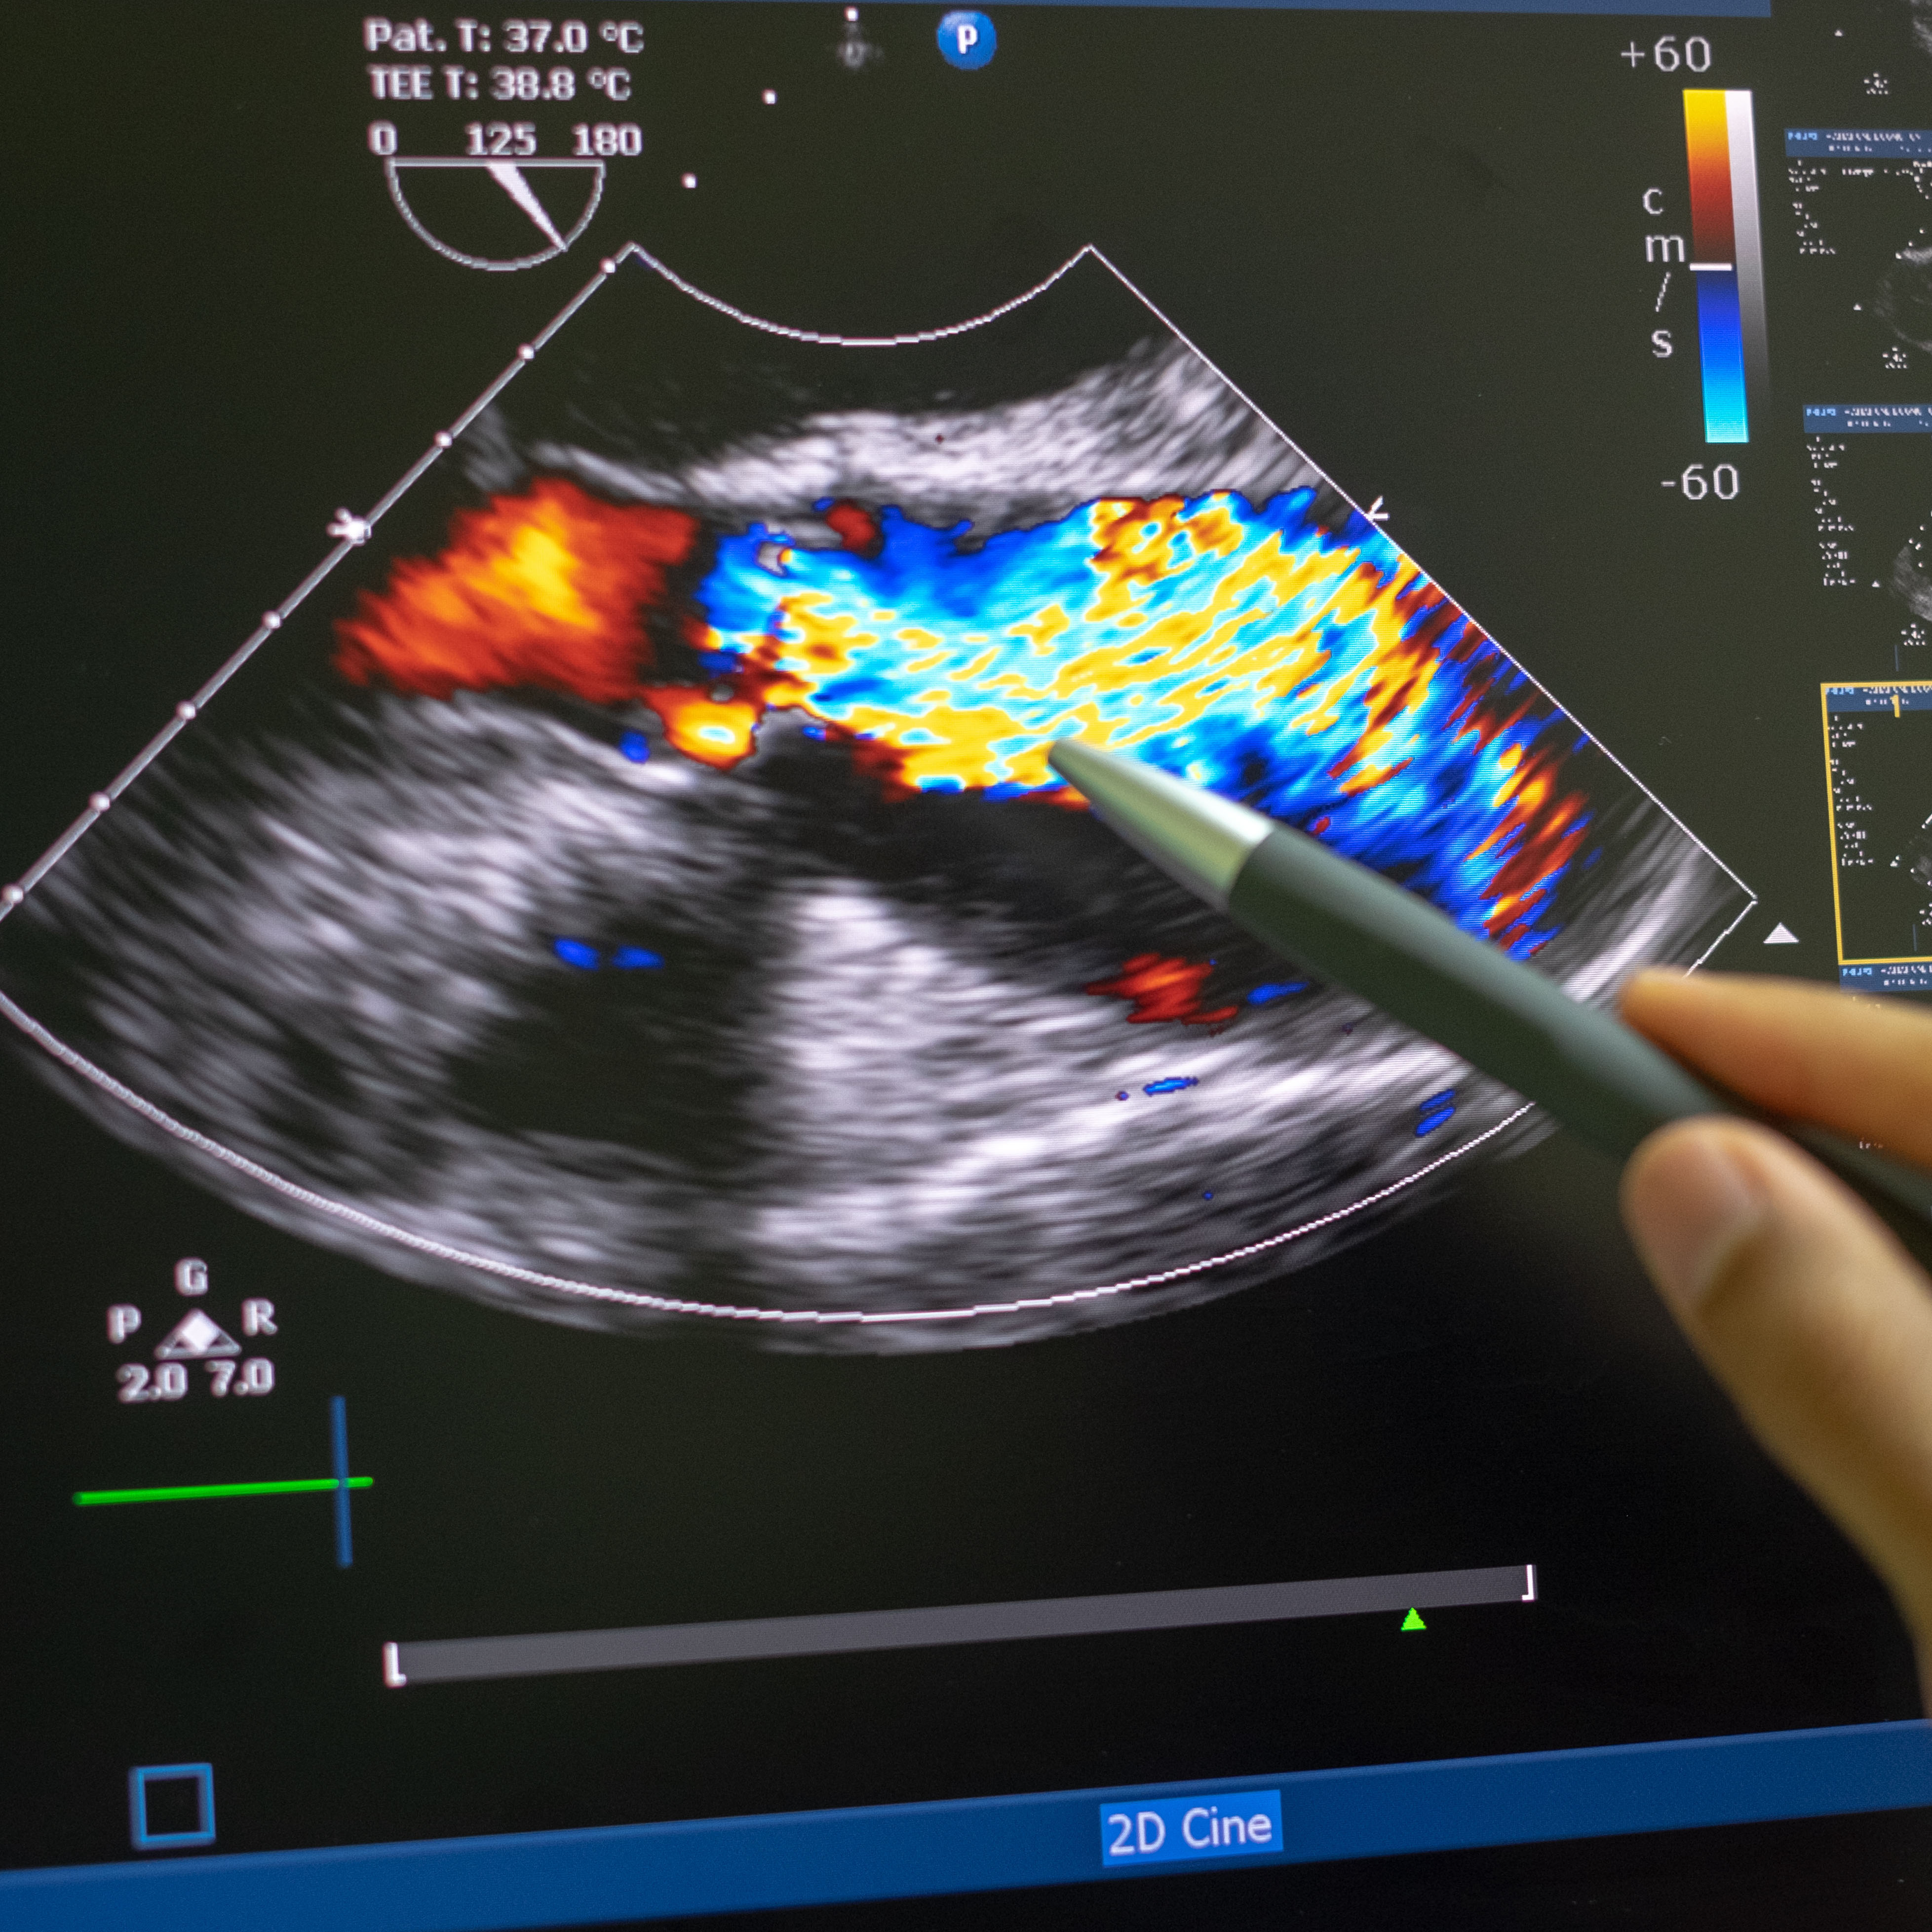

随着病情的发展,它会导致部分心肌变厚。维卢甘蒂博士指出,这种厚度可能发生在心脏的任何地方,但通常发生在分隔左右心室(心脏底部的两个心室)的室间隔内。当这种情况发生时,血液流动就会受阻。这被称为阻塞性HCM,它使心脏更难将血液泵到身体的其他部位。维卢甘蒂医生说:“心脏实际上工作正常,但就像在推墙一样。”“随着时间的推移,这可能会导致症状。”

久而久之,HCM也会引起心脏衰竭在这种情况下,心脏变得过于僵硬,无法填满正常数量的血液。这使得心脏向身体其他部位输送足够的血液变得更加困难。结果是:呼吸更加急促和疲劳,腹部、腿部和脚踝肿胀。HCM还会干扰从心脏左心房到左心室的血液流动。这种情况称为二尖瓣疾病,会加重HCM的症状。